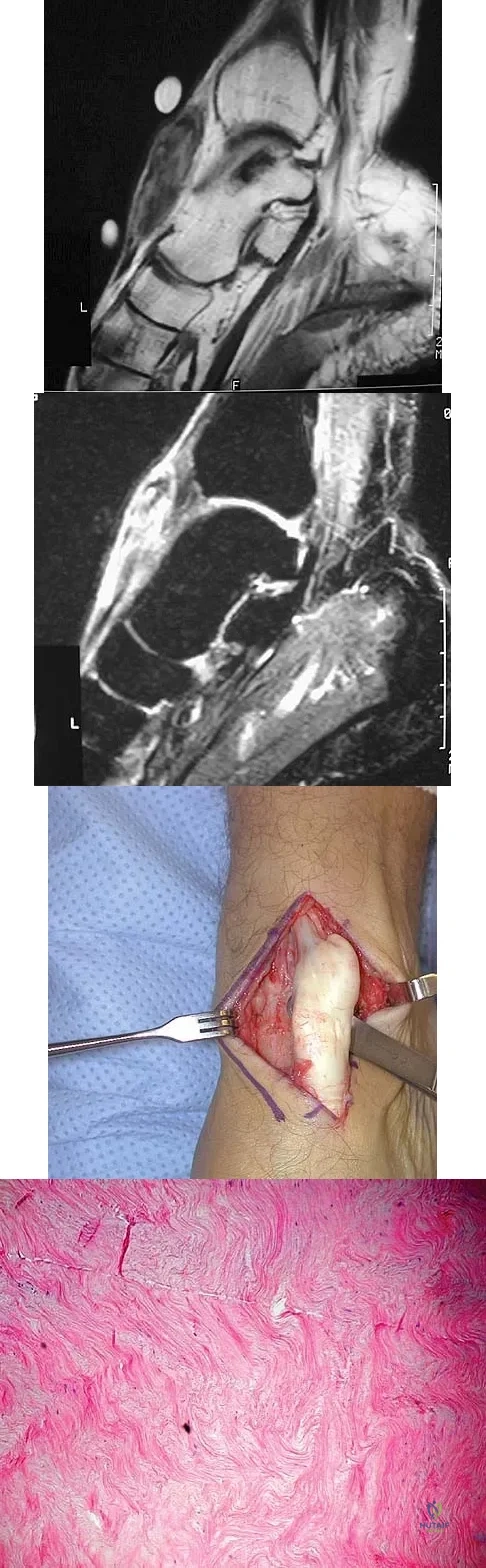

A 28-year-old woman has left shoulder pain and a tender soft-tissue mass. Based on the MRI scan and biopsy specimens shown in Figures 74a through 74c, what is the most likely diagnosis?

A 40-year-old man has a palpable mass over the dorsum of the ankle. He reports no history of direct trauma but notes that he sustained a laceration to the middle of his leg 6 weeks ago. Examination reveals a 4-cm x 1-cm mass. T1- and T2-weighted MRI scans are shown in Figures 12a and 12b. An intraoperative photograph and biopsy specimen are shown in Figures 12c and 12d. What is the most likely diagnosis?